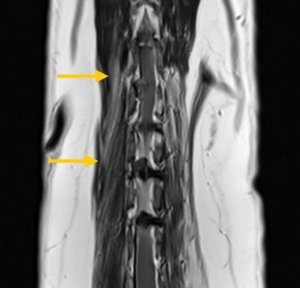

T2加權冠狀切面(T2 COR):清楚顯示兩處椎間盤物質突出(IVD extrusion),位置分別為T12-T13 和 L1-L2 節段,皆在脊髓右側形成壓迫。